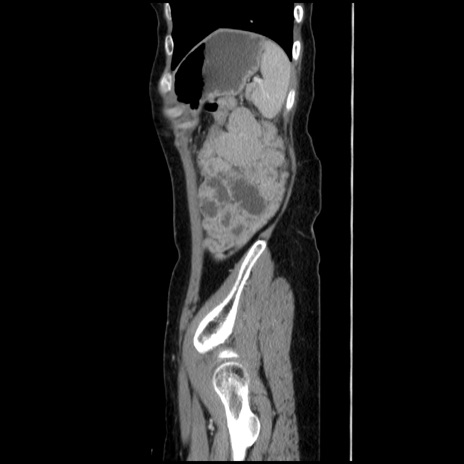

症例32(矢状断像)

【症例】40歳代 女性

【主訴】上腹部痛、嘔気・嘔吐

【現病歴】約9時間前頃から急に上腹部痛、嘔気、嘔吐が出現。改善しないため救急要請。

【既往歴】子宮頚癌(広汎子宮全摘術、放射線療法)、腸閉塞

【身体所見】腹部:平坦、軟、腸雑音亢進、上腹部を中心に腹部全体に圧痛あり。

【データ】WBC 8400、CRP 0.03